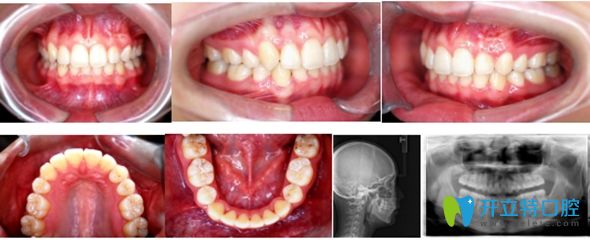

用時(shí)20個(gè)月,小哥哥矯正結(jié)束,開(kāi)始佩戴透明保持器。

小哥哥在北京佳美口腔正畸牙齒術(shù)后圖

<小哥哥說(shuō):牙齒矯正用痛并快樂(lè)形容,太貼切了!效果如上>      ↑↑